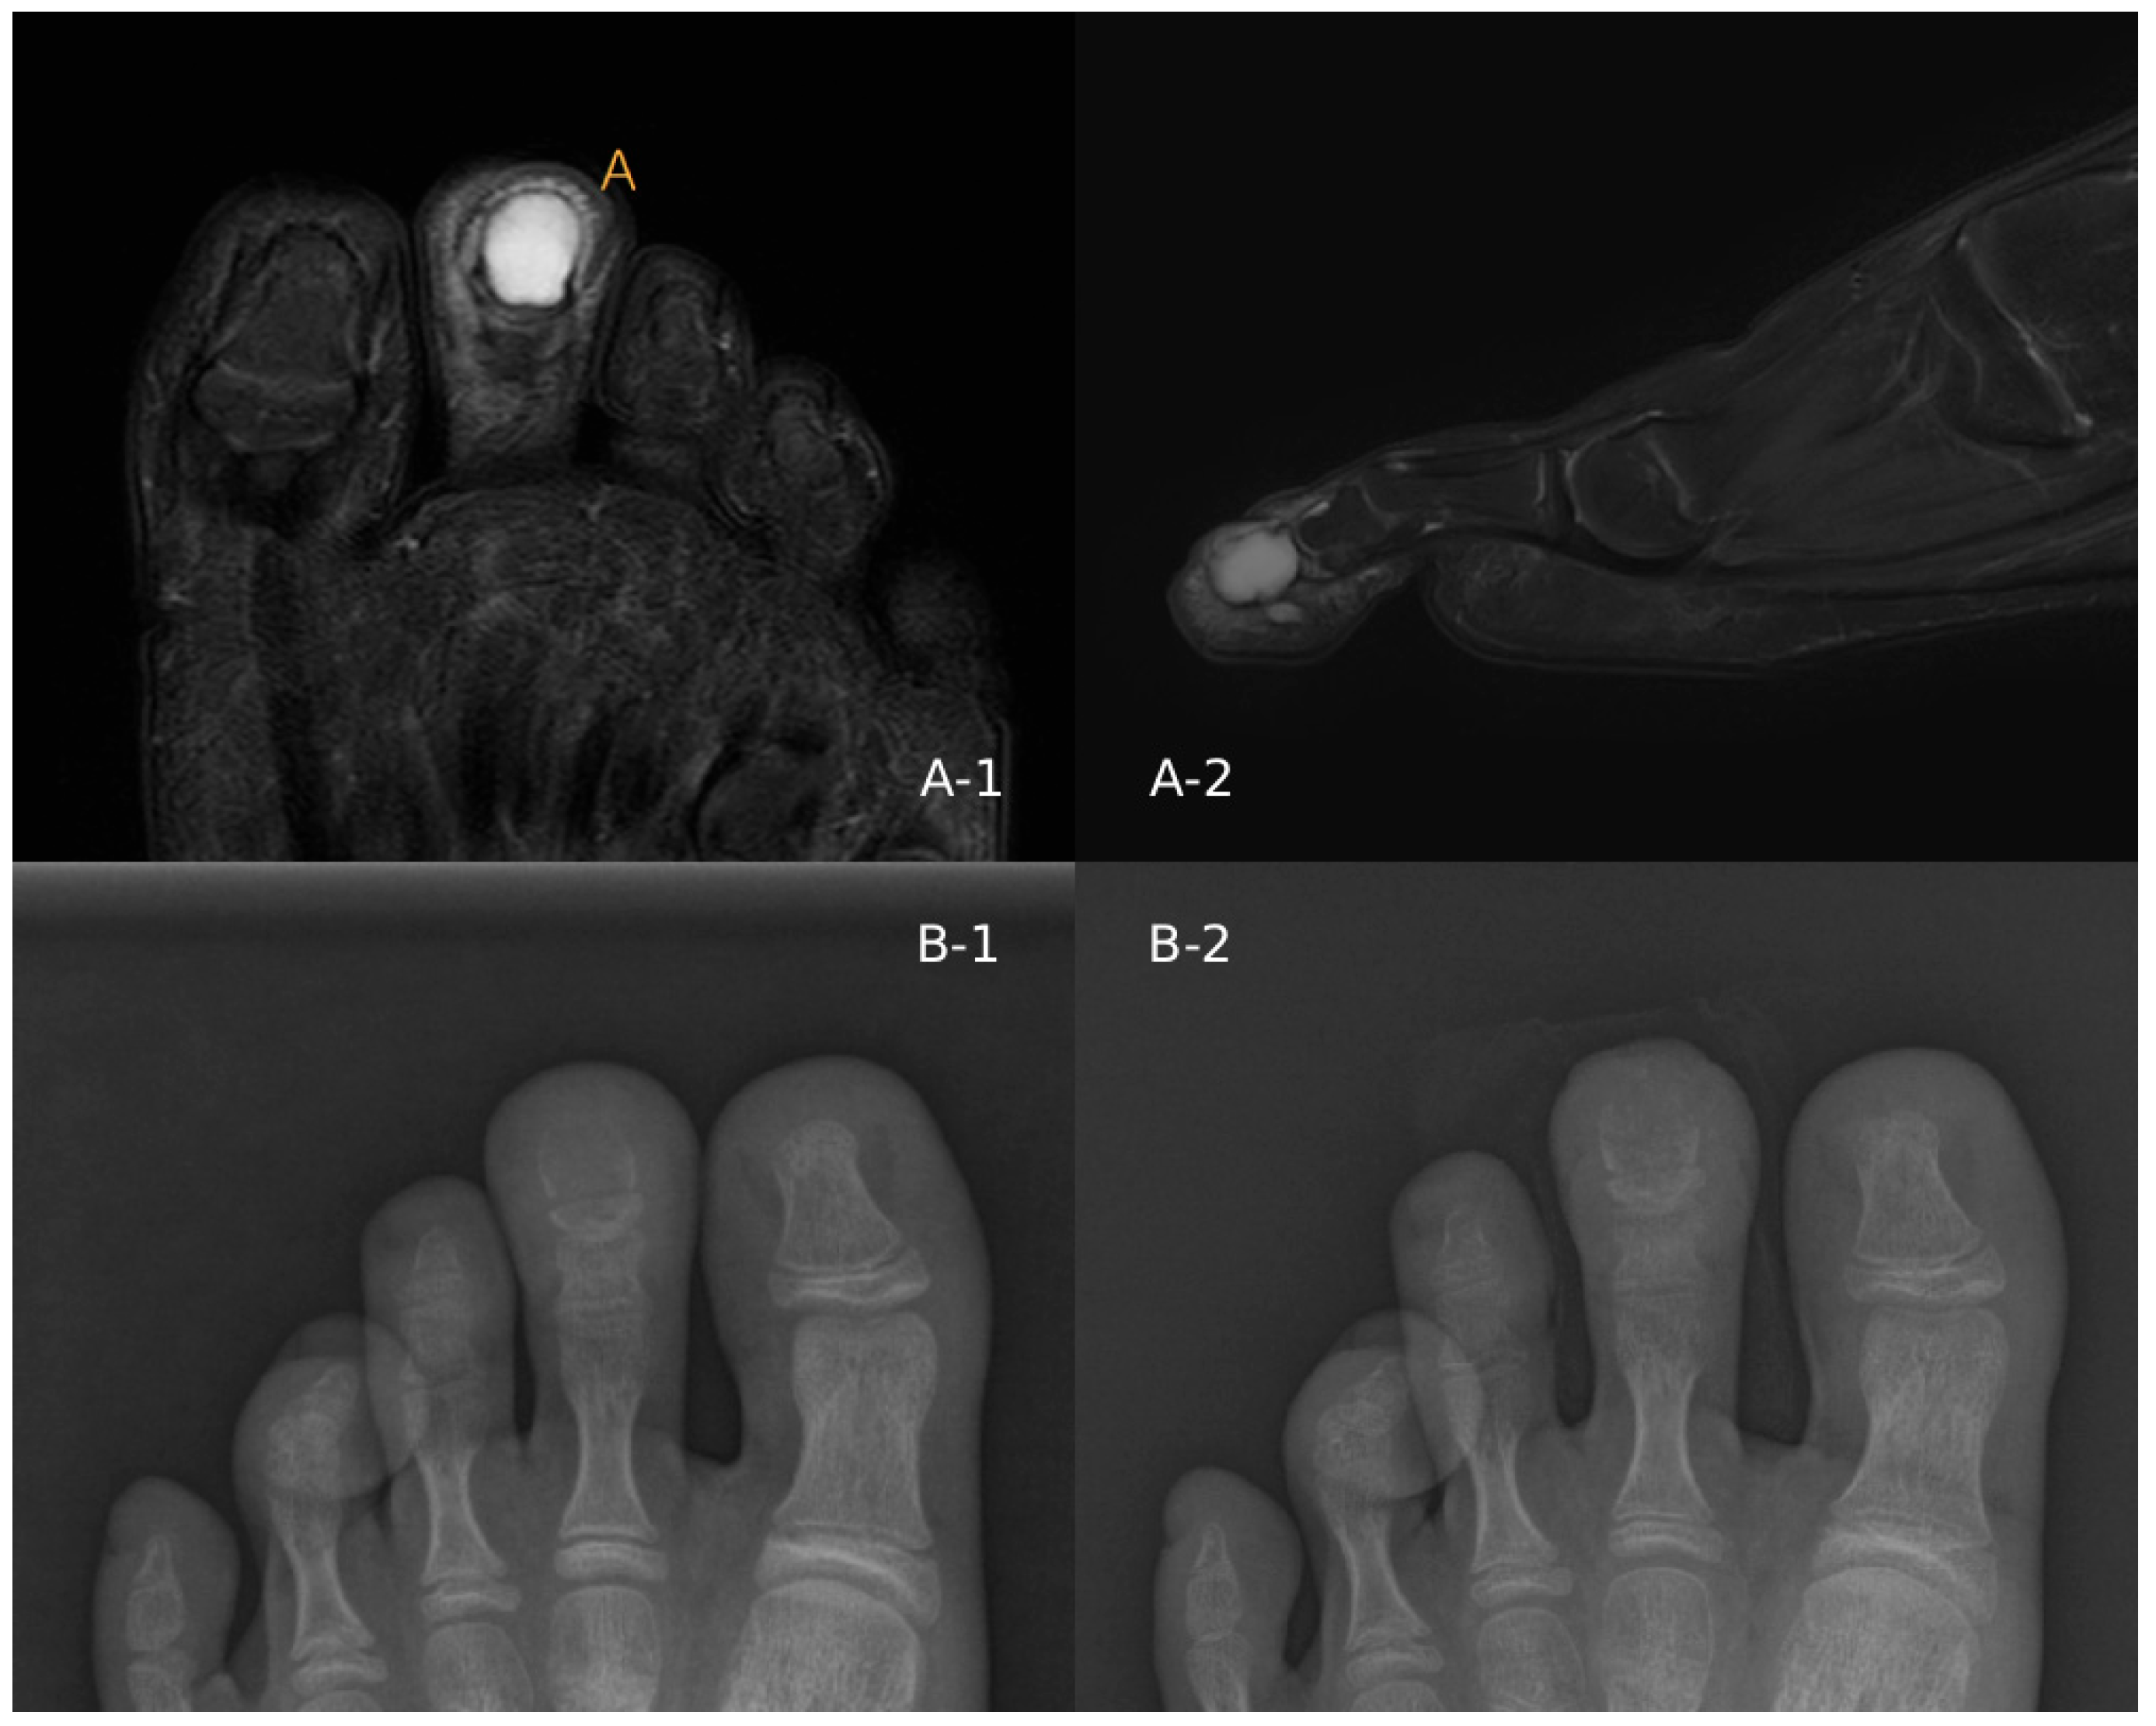

Recurrent Chondromyxoid Fibroma of the Second Toe Distal Phalanx Treated with Distal Phalangectomy: A Case Report

2. Case Report